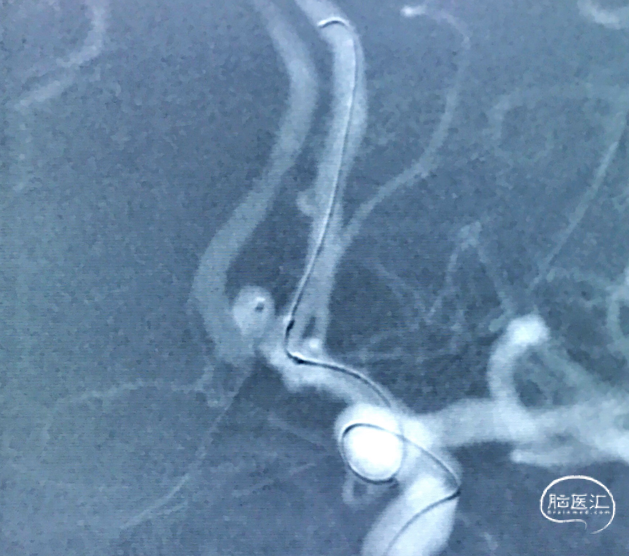

选用HyperForm™封堵球囊系统4mm×7mm,先将球囊导管到位,使球囊位于左侧大脑前A1和前交通交汇处,以便球囊充盈后可充分覆盖瘤颈口。后将头端45°预塑形的Echelon™ 10微导管到位,用于后续弹簧圈填塞

微导管到位

球囊及微导管到位